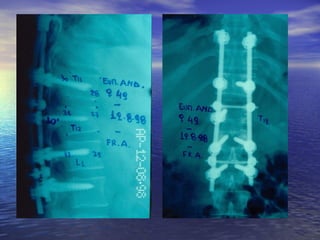

ΘΘωωρραακκοο –– οοσσφφυυϊϊκκάά

κκααττάάγγμμαατταα ΘΘ1111--ΟΟ11

• ααππόό ββίίααιιηη υυππέέρρκκααμμψψηη κκααιι σσττρροοφφήή

• εείίννααιι σσυυννήήθθωωςς αασσττααθθήή ((εευυάάλλωωττοοιι οοιι αασσθθεεννεείίςς

σσττιιςς σσττρροοφφιικκέέςς κκιιννήήσσεειιςς))

• ππττώώσσηη ααππόό ύύψψοοςς,, ττρροοχχααίίοο ααττύύχχηημμαα,,

δδιιααττιιττρρααίίννοονν ττρρααύύμμαα

• σσυυννοοδδεεύύοοννττααιι ααππόό κκαακκώώσσεειιςς σσππλλάάχχννωωνν

((ήήππααττοοςς,, σσππλληηννόόςς,, εεννττέέρροουυ,, κκοοιιλλιιώώνν,,

ααγγγγεείίωωνν)) ρρήήξξηη δδιιααφφρράάγγμμααττοοςς

ΘΘωωρραακκοο –– οοσσφφυυϊϊκκάά κκααττάάγγμμαατταα ΘΘ1111--ΟΟ11 • ααππόό ββίίααιιηη υυππέέρρκκααμμψψηη κκααιι σσττρροοφφήή • εείίννααιι σσυυννήήθθωωςς αασσττααθθήή ((εευυάάλλωωττοοιι οοιι αασσθθεεννεείίςς σσττιιςς σσττρροοφφιικκέέςς κκιιννήήσσεειιςς)) • ππττώώσσηη ααππόό ύύψψοοςς,, ττρροοχχααίίοο ααττύύχχηημμαα,, δδιιααττιιττρρααίίννοονν ττρρααύύμμαα • σσυυννοοδδεεύύοοννττααιι ααππόό κκαακκώώσσεειιςς σσππλλάάχχννωωνν ((ήήππααττοοςς,, σσππλληηννόόςς,, εεννττέέρροουυ,, κκοοιιλλιιώώνν,, ααγγγγεείίωωνν)) ρρήήξξηη δδιιααφφρράάγγμμααττοοςς